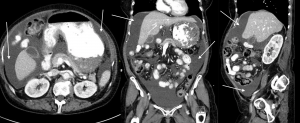

Home » Ascites: Abdominal/Pelvic CT-Scan With IV & Oral Contrast » Example 2 75 M